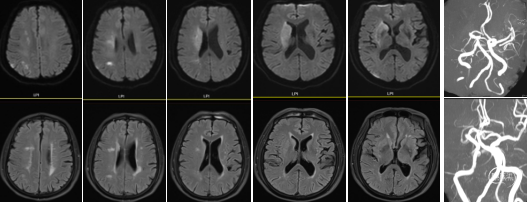

急诊绿色通道完善脑MR:1.右侧额顶叶、基底节区、岛叶、颞枕叶多发急性期梗死;2.右侧大脑中动脉重度狭窄或闭塞。